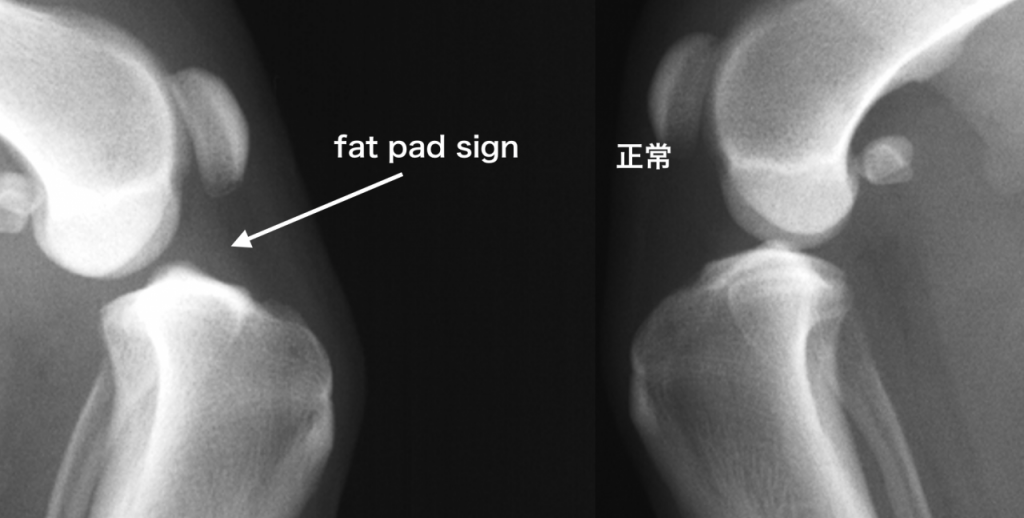

大腿骨と脛骨の位置のずれ(drawer sign:ドロワーサイン)

炎症による関節液貯留の結果生じる、脂肪の圧迫像(fat pad sign:ファットパッドサイン)を確認します。